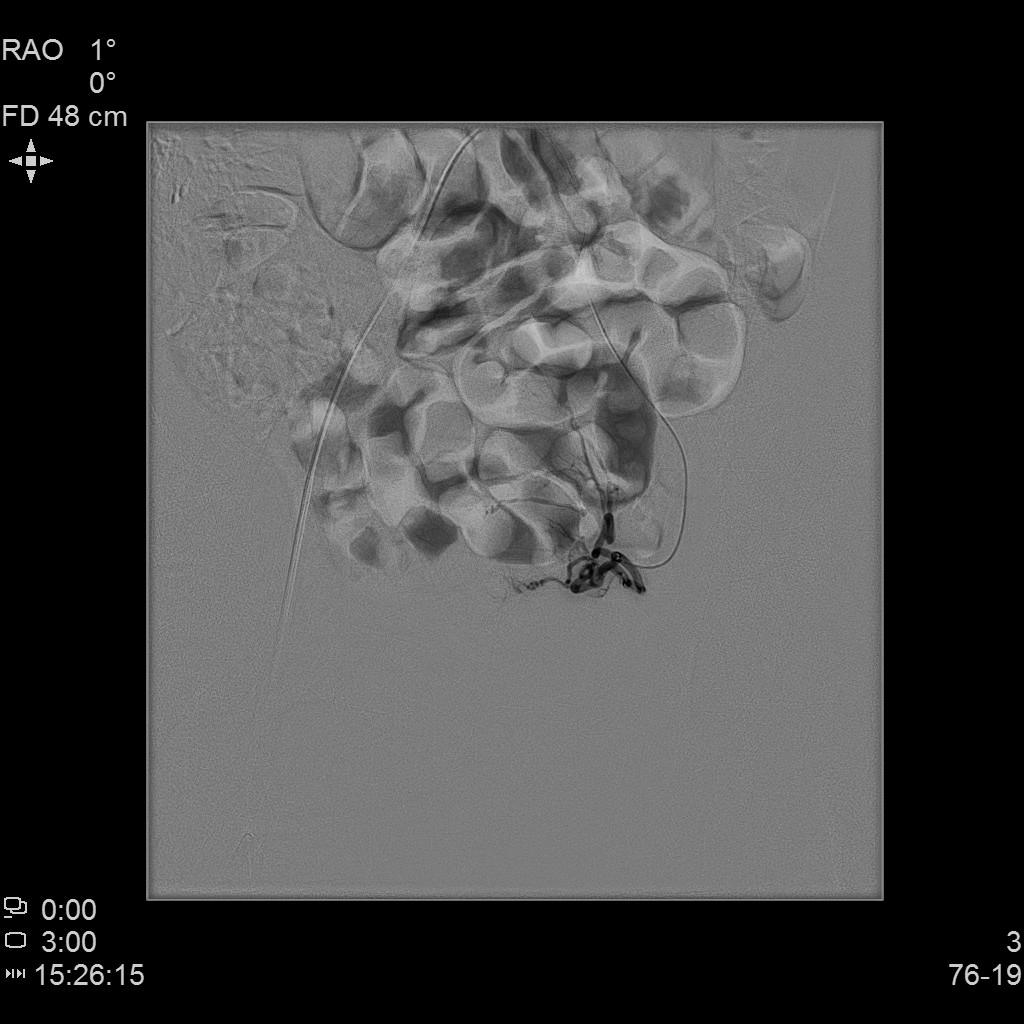

- 插管至右侧髂内动脉造影,显示右侧子宫动脉

- 插管至右侧子宫动脉,显示子宫右侧病灶情况